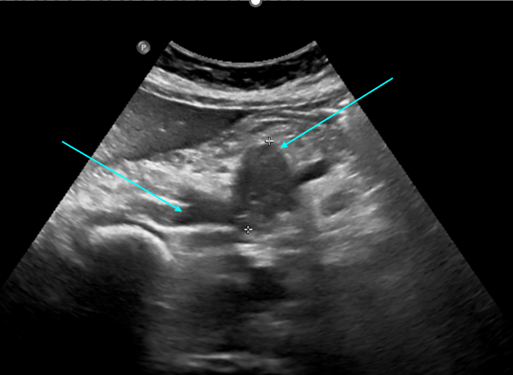

Eco-doppler abdominal

Ecografía adbominal

Ecografía abdominal

Hallazgos radiológicos: